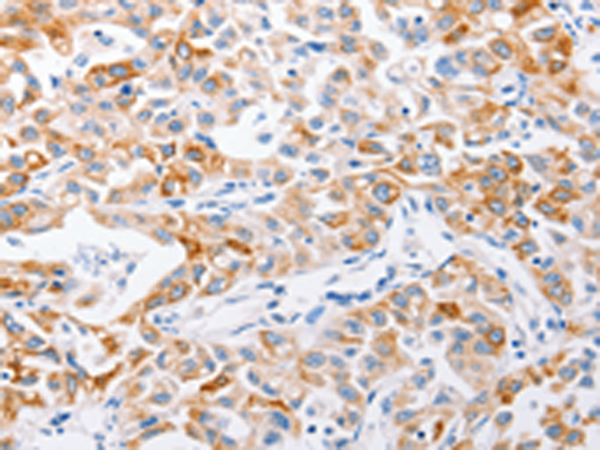

分类: 科研抗体货号: P11022别名: MCM-BP; C10orf119应用: WB,IHC反应种属: Human, Rat